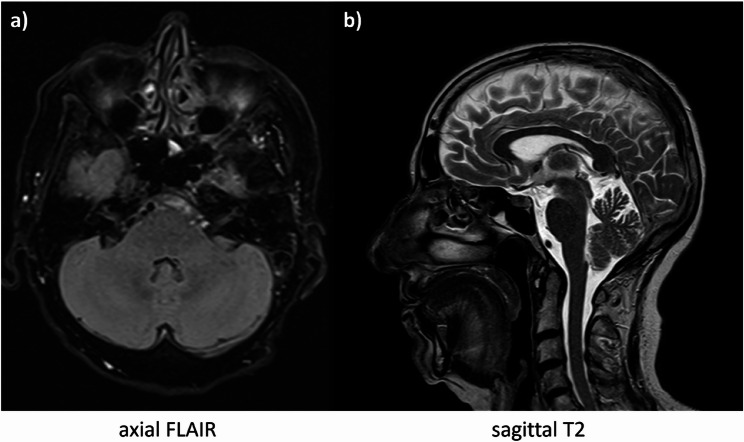

Case presentation: A 68-year-old female patient presented with subacute onset gait impairment and concomitant vertigo. Gaze induced nystagmus, ataxia and limb dysmetria became objectifiable. A broad diagnostic workup, including liquor puncture, whole-body positron emission tomography, antibody serology and most notably thin-layer magnetic resonance imaging remained unconclusive. Only a more detailed examination of chronic hypokalemia with the detection of severe magnesium deficiency under the intake of proton pump inhibitors and a recent gastrointestinal infection found a causal treatment through electrolyte substitution.